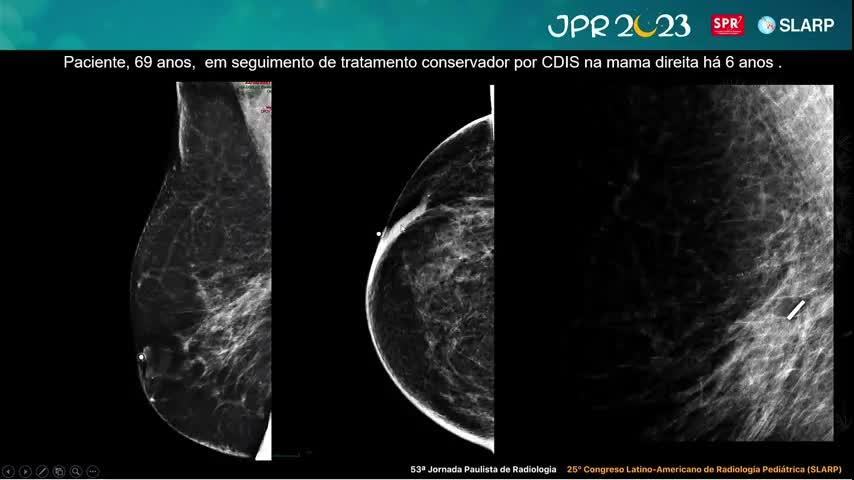

Caso 3: Mama